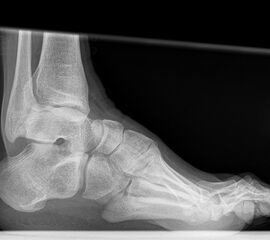

Fersenbein lateral

Positionierung:

• Patient in Seitenlage.

• Fuß mit der Außenseite aufliegend.

• Ferse liegt parallel zum Tisch.

• Röntgenröhre 90° zur Senkrechten.

• Zentralstrahl von lateral nach medial, zentriert auf das Fersenbein ca. 1-2 Querfinger distal der Malleolen.

Kennzeichen des Röntgenbildes:

• Seitliche Darstellung des Fersenbeins mit scharfen Knochenkonturen.

• Gut einsehbares unteres Sprunggelenk (Articulatio talocalcaneonaviculare).

• Gut einsehbares Gelenk zwischen Calcaneus und Os cuboideum.

Besondere Bemerkungen zum Beispielbild:

• Darstellung der Kalkaneus seitlich.

• Kleiner Traktionssporn im Insertionsbereich der Achillessehne.

• Großes Os trigonum dorsal des Talus.